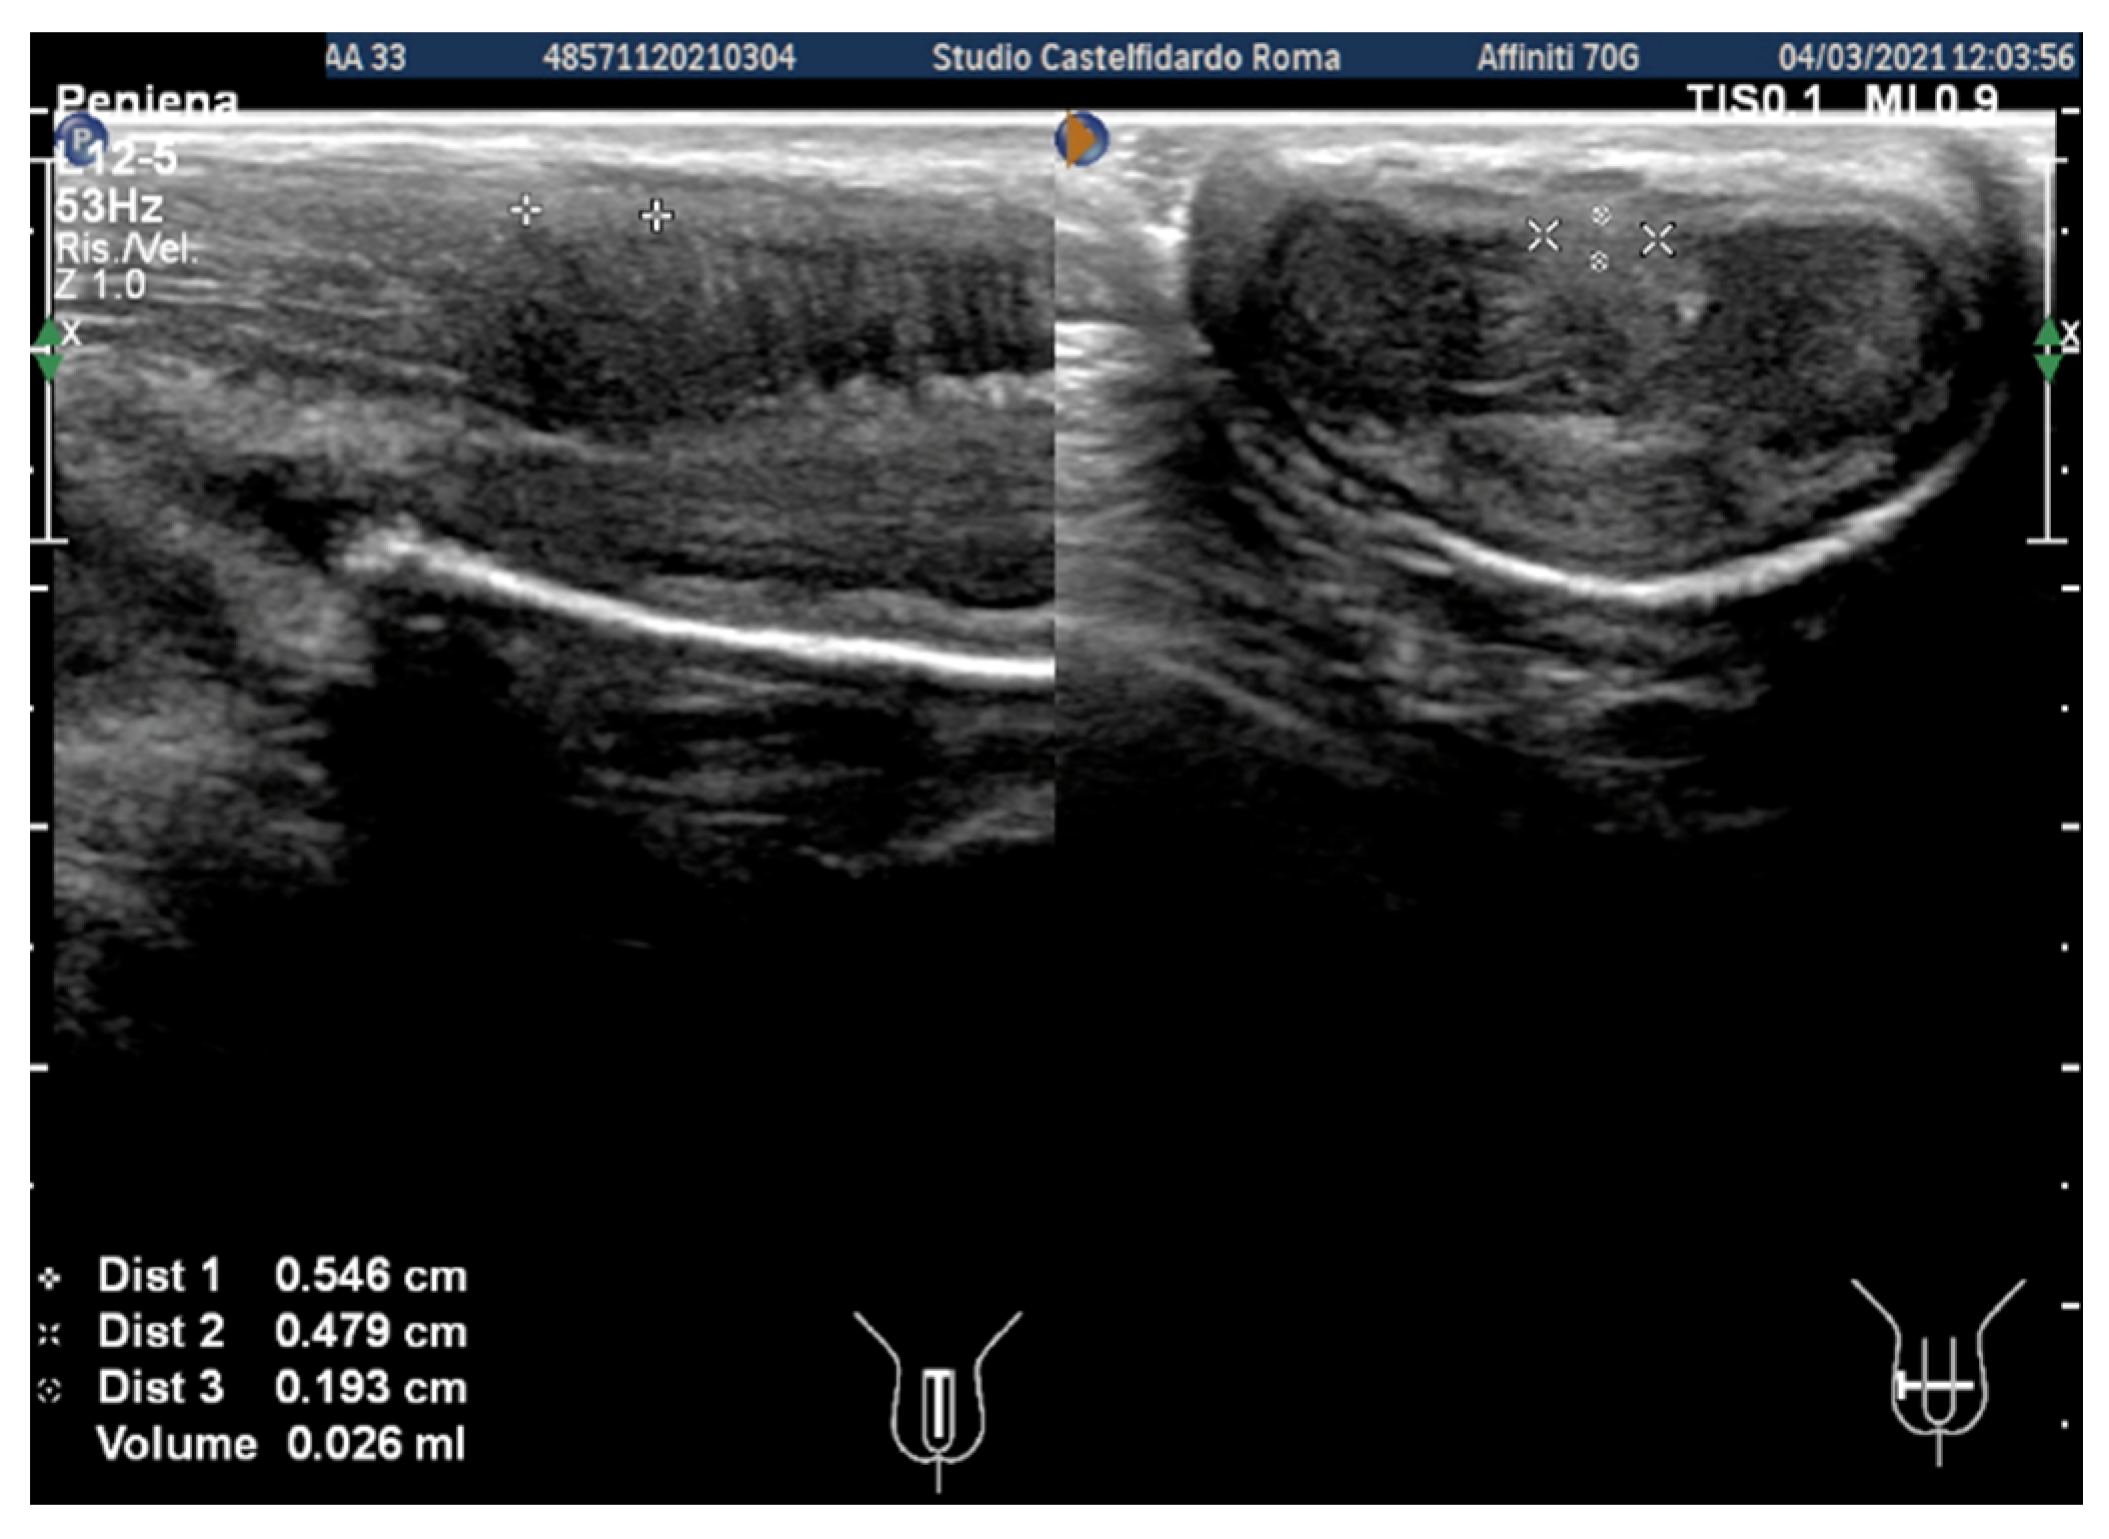

| 3 | 30 years | Left varicocele | Proximal third | (A) 12.2 × 11.2 × 2.81 mm volume = 203 mm3 (B) No plaque detected | (A) No penile deformation (B) No penile deformation | VAS score = 5 Pain disappeared after 4 months | 26 > 26 | 4 months | Orally: propolis 600 mg + bilberry 160 mg + silymarin 400 mg + ginkgo biloba 250 mg + vitamin E 800 IU/daily for 4 months + topically: diclofenac gel 4%/2× daily for 4 months Note: Penile injections not needed |